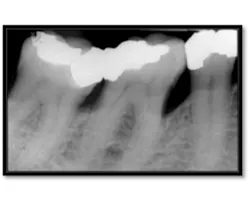

Initial perio charting (above left), Pretreatment radiograph (above right)

As you can see, the extent of bone loss on the mesial is significant, almost to the apex.14 months post treatment: